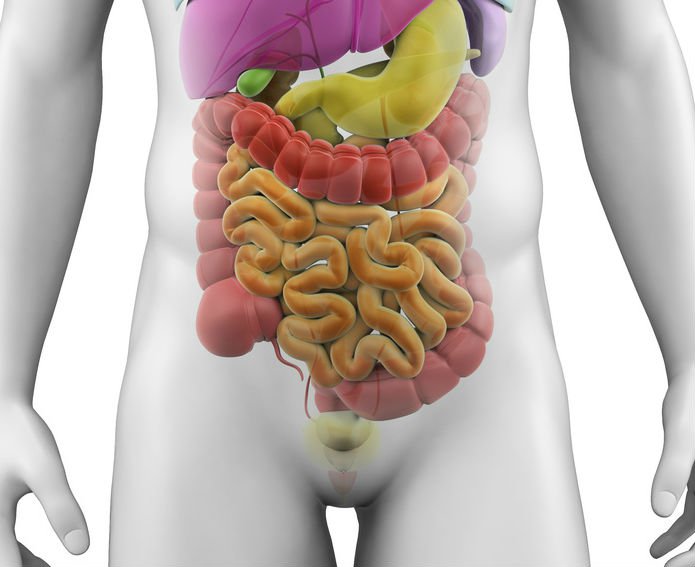

Иллюстрации и информация о симптомах острого кишечного непроходимости